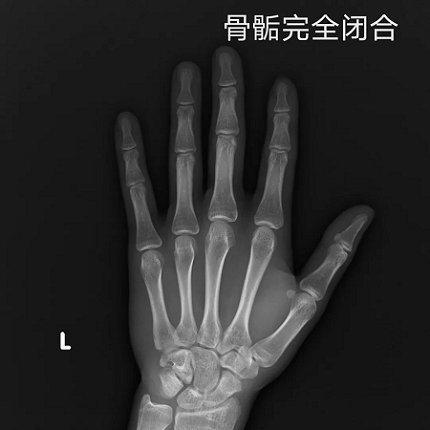

在儿童生长发育门诊,遇到过不少这样的情况,爸爸妈妈个子都不低,但孩子的身高始终都比同龄人低一截,孩子可能是“晚长”吧,许多家长会抱着侥幸的心理等等看。14岁的萌萌就是这样的一个例子,爸爸1米76,妈妈1米62,正常情况下萌萌现在应该1米6,但是自从她长到1米5之后今年就一直没长个了。趁着暑假,妈妈带萌萌到医院检查,可是拍了骨龄片之后发现骨骺线快闭合了,孩子长个的空间已经很少了......

▲ 骨龄片对比图

虽然“晚长”的情况存在,但这只是个例。随着现代社会经济的发展,孩子普遍存在营养过剩,不少孩子甚至十三四岁骨骺线就已闭合,“晚长”的现象少之又少,所以家长们不能盲目等待,拿孩子的未来赌“晚长”的概率,最终错过孩子身高的干预时机。

另外提醒家长们,如果孩子出现“性早熟”表现或者开始青春期发育时仍然身高偏低,更要及时就医,因为开始发育后骨龄会迅速成熟,身高增长的时间就很有限了。医学研究表明:一旦骨骺闭合,无论任何方法都不可能再长高。